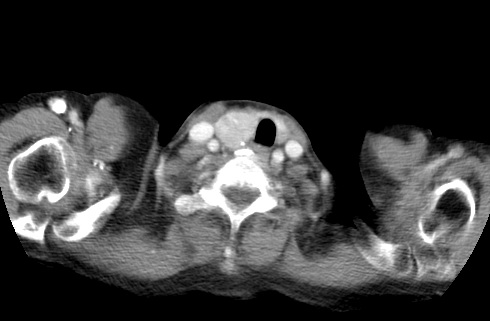

标题: CT23982:女67岁,胸部扫描时发现,甲状腺瘤? [打印本页]

标题: CT23982:女67岁,胸部扫描时发现,甲状腺瘤?

右侧甲状腺腺瘤!支持!不排除甲状腺癌可能!建议手术切除!

右侧甲状腺占位性病变,性质待定(甲状腺腺瘤?);建议:必要时行进一步检查。

右侧甲状腺占位性病变,性质待定(甲状腺腺瘤?);

右侧甲状腺占位性病变,性质待定(甲状腺腺瘤?);建议穿刺活检。

右侧甲状腺占位性病变,甲状腺腺瘤可能,建议穿刺活检。